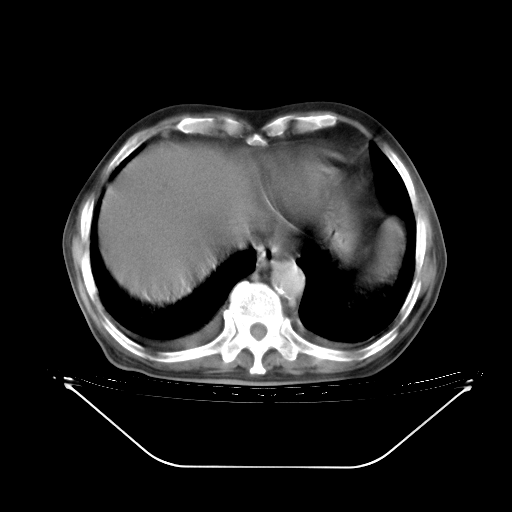

今天复查肺部CT,发现双肺广泛磨玻璃样改变。所以我把3月19日和5月9日相隔50天的肺部CT上传。请大家会诊。

5月9日肺部CT(在4月27日齐鲁医院肺部CT描述部分肺组织磨玻璃样改变,12天后肺组织广泛磨玻璃样改变)

2009年5月9日肺部CT

大致读了系列胸部CT:纵隔窗无明显异常,肺窗:从4、27至今:主要是双肺中下野外带可见毛玻璃样改变,目前处于急性肺泡炎阶段,至于原因考虑1、结替组织或胶原血管性疾病所致?2、恶性疾病如恶组在肺部所致的表现或细支气管肺泡癌?3、药物或其它原因如肺蛋白沉着症所致肺泡炎目前不太可能?总之,明天就去请我院的呼吸科、感染科、血液科和临免专家会诊哈。